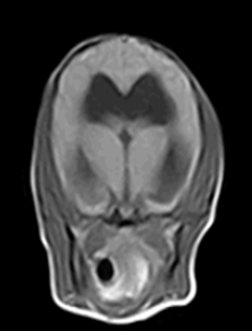

| T1 | T2 |

![]() | ![]() |

| ๋์ฒ์์ก์ด ์๋ lateral ventricle์ด ํ์๊ฒ ๊ด์ฐฐ๋จ. |

T2์ ์๋์์ ํ์๊ฒ ๋ณด์ด๋ ๋ถ์(=ํ์ดํ) โ ๋์ฒ์์ก์ด ์์ด์ผ ํ ๋ถ์์ ๋ฌผ์ด ์ฐธ.